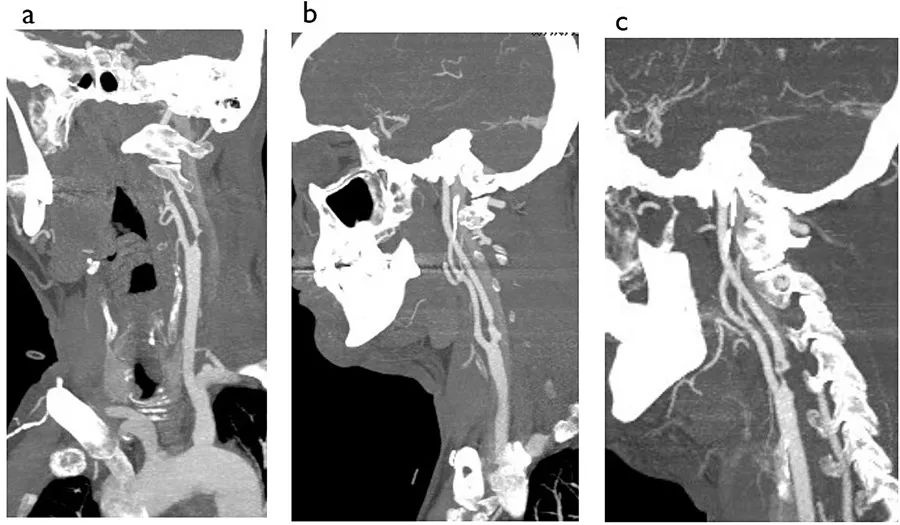

例8

图8  65岁男性,左侧大脑半球短暂性脑缺血发作,图为包括主动脉弓、颈部和颅内动脉的CTA,A:斜冠状位;B:矢状位;C:斜矢状位

不难看出,本例患者左颈动脉球和颈内动脉起始处可见严重不规则狭窄,而这也是患者出现短暂性脑缺血发作的罪魁祸首。

例9

图9  另一例左侧大脑半球短暂性脑缺血发作患者,A:斜矢状位;B:斜冠状位

本例患者的左颈动脉区域可见串联状病变,左颈内动脉起始处有密集的钙化斑块,造成血管的严重狭窄,同时左侧颈总动脉也可见严重狭窄(图中箭头)。不过,超声扫描并未检出左颈总动脉的病变。这种在血管分叉处密集的不规则斑块钙化会使测量精确的管腔尺寸变得更困难。